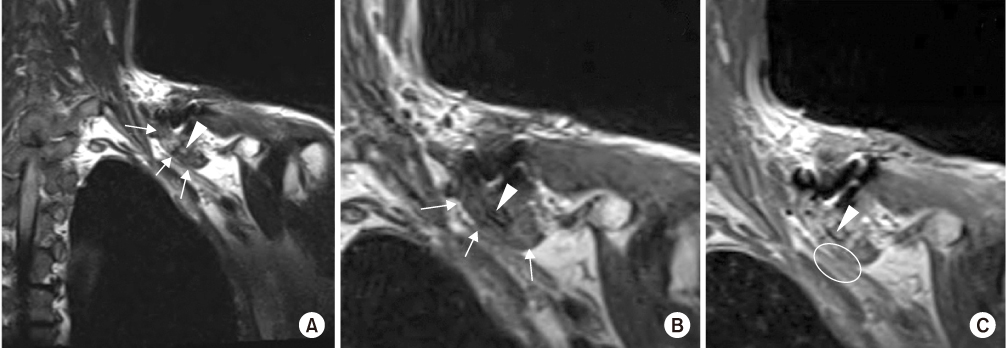

Postoperative neurovascular status was intact, and we found no abnormal findings until postoperative day 3. On postoperative day 4, the patient presented with numbness in the left hand and decreased strength. A grade 1/5 in thumb extension and flexion, wrist extension, and finger extension, flexion, and abduction was found in addition to a grade 3/5 in wrist flexion and elbow flexion and extension. A haematoma formation at the operation site was suspected because of the acute onset of symptoms on postoperative day 4. On postoperative day 5, an ultrasound was performed for evaluation of a possible haematoma, but no definite mass or haematoma was found around the clavicle. On postoperative day 6, diffusion magnetic resonance imaging (MRI) was performed to evaluate for possible acute stroke, but there was no evidence of acute infraction. Additionally, on postoperative day 6, cervical spine MRI was performed to evaluate the cervical spine. Cervical spine MRI demonstrated a fibrotic mass lesion around a small bony fragment inferior to the clavicle. This lesion was compressing the adjacent brachial plexus causing signal changes within the brachial plexus (Fig. 3). Based on the MRI findings, we removed the implant and made a superior angulation to decompress the brachial plexus. There was no haematoma intraoperatively, and we left grafted bone. We put a Velpeau sling on the patient's left shoulder after surgery (Fig. 4).

Fibrotic mass lesion margin (white arrows) around the small bony fragment (white arrowheads) inferior to the clavicle, which compressed the adjacent brachial plexus and caused signal changes within the brachial plexus (white circle) on the (A) cervical spine T2 coronal image, (B) cervical spine T1 coronal image, and (C) cervical spine T1 enhanced coronal image.